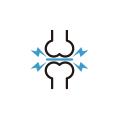

주사치료

주사치료

원인 신경 차단

원인 신경 차단

실시간 영상 확인

실시간 영상 확인

빠른 통증 감소

빠른 통증 감소

빠른 일상생활 복귀

빠른 일상생활 복귀

초음파로 병변 확인

초음파로 병변 확인

정상 조직 손상 최소화

정상 조직 손상 최소화

방사선 노출 최소화

방사선 노출 최소화

실시간 영상 유도 시술

실시간 영상 유도 시술

신경·관절 위치 정밀 확인

신경·관절 위치 정밀 확인